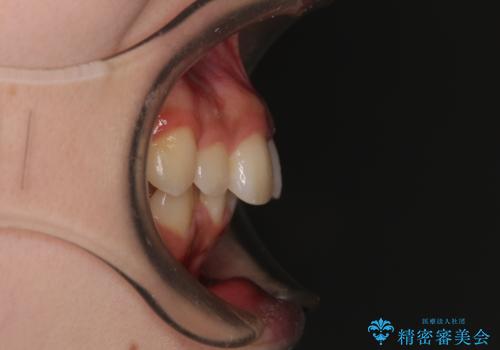

- 上顎前歯の突出感を気にして来院された患者様です。

上下左右第一小臼歯4本を抜歯して、積極的に口元を引っ込めるよう、ワイヤー装置にて矯正治療を行うこととしました。

抜歯矯正により、下唇が前方に突出した感覚が大幅に改善されました。